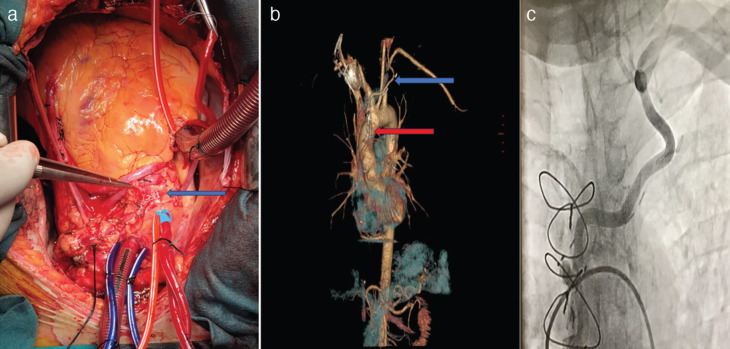

A Novel Approach for the Treatment of Subclavian Steal Syndrome in a Patient Undergoing Coronary Artery Bypass Grafting